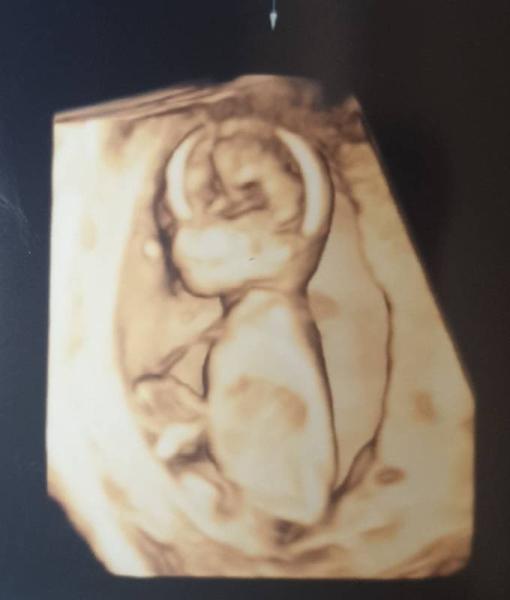

Hallo ihr Lieben, Ich hatte heute den Ultraschall für den NiP Test. Alles gut und alles wie es sein soll. Baby wächst und wächst und tobt Uns hat sich ziemlich deutlich ein kleiner Junge gezeigt Mein Sohn ist völlig aus dem Häuschen und freut sich sehr. Uns war es ganz egal, Hauptsache gesund Nächste Woche bekomme ich dann noch die Blutergebnisse. Ich gehe jetzt mal positiv daran, schließlich war nix auffällig. Sogar die Nackenfalte war noch zu sehen und absolut im Rahmen. Ich freu mich so und für euch alle auch!!! Liebe Grüße Claudi

Hab noch ein Bildchen

Wow was für ein tolles Bild , echt Wahnsinn was man heutzutage alles erkennen kann! Glückwunsch zum kleinen Jungen! Schön das alles in Ordnung ist